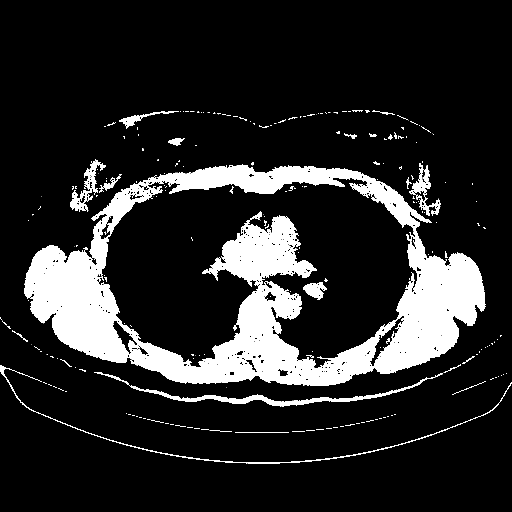

Original NATIVE CT scan (input)

Full window (WL 1023.5, WW 4095 β†’ Low βˆ’1024, High +3071)

Actual HU range: [-1024.0, 3071.0]